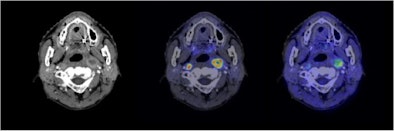

![]() |

| Semiconductor PET images (coregistered with CT images) of nasopharyngeal cancer, using FDG (center image) and F-18 fluoromisonidazole (FMISO) (right image) tracers. The new PET system clearly reveals the different distribution between metabolism and hypoxia in the left neck lymph node metastasis. |